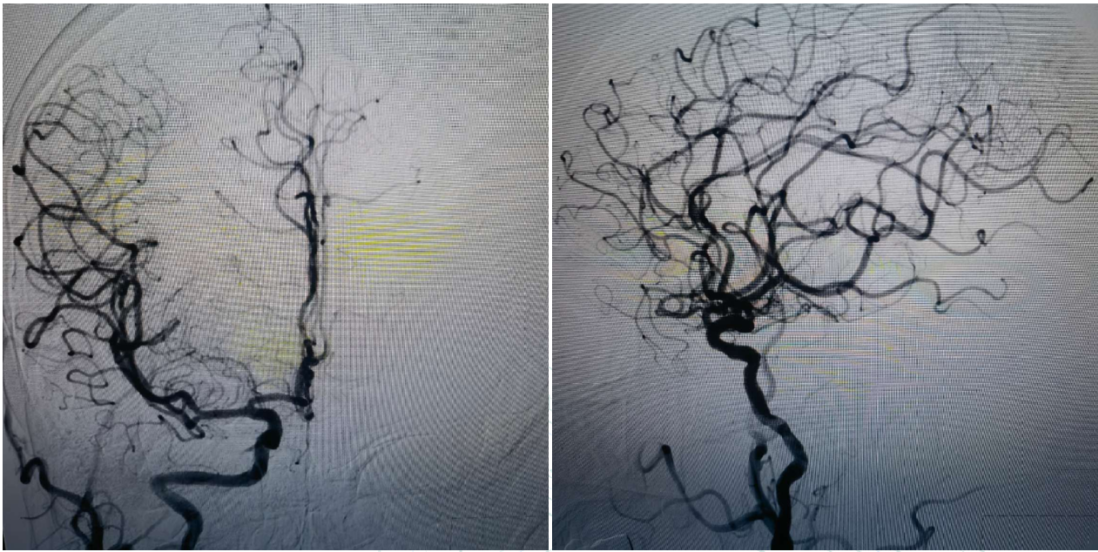

To further manage severe stenosis at the origin of the right ICA, the aspiration catheter was withdrawn. A distal protection device was deployed through the 8F guiding catheter, which was then retracted to the common carotid artery. A peripheral balloon dilation catheter was advanced along the protection guidewire to the stenotic segment for angioplasty. After balloon dilation, a Wallstent was delivered along the protection guidewire and precisely deployed at the stenotic site. Post-deployment angiography showed good stent apposition, with a residual stenosis rate of approximately 20%. Antegrade blood flow and intracranial perfusion improved, achieving TICI grade 3 flow.

Postoperative Angiography

The right MCA, ACA, and their branch arteries were well visualized, with antegrade flow of TICI grade 3 and no signs of acute vascular occlusion.